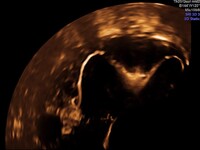

- 3D υπέρηχος μήτρας, ώστε να αποκλειστεί η ύπαρξη συγγενών ανωμαλιών της μήτρας,

Για τους λόγους αυτούς, τα τελευταία χρόνια αναπτύχθηκε η υστερο-σαλπιγγογραφία με τη χρήση υπερήχων (HyFoSy), μια σύγχρονη μέθοδος με αξιοπιστία παρόμοια με την κλασική σαλπιγγογραφία, χωρίς όμως τα μειονεκτήματα της παλαιάς μεθόδου.